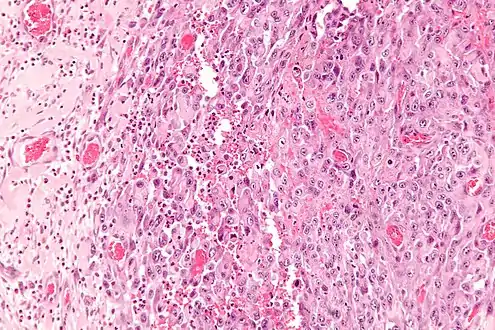

Histologically, epithelioid sarcoma forms nodules with central necrosis surrounded by bland, polygonal cells with eosinophilic cytoplasm and peripheral spindling.[3] Epithelioid sarcomas typically express vimentin, cytokeratins, epithelial membrane antigen, and CD34, whereas they are usually negative for S100, desmin, and FLI1 (FLI-1).[3] They typically stain positive for CA125.[4]

High mag.